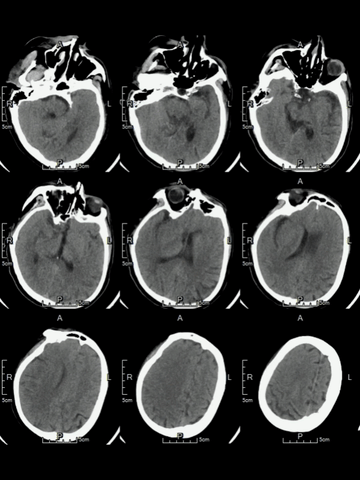

急诊多模式CT

CT平扫:右侧岛叶和额叶可见低密度,范围相对较大。

颅脑CTA:右侧颈内动脉分叉部闭塞,累及MCA和ACA近端,颈内动脉分叉部可见血管高密度影。

颈部CTA:未及明确异常。

CTP:右侧半球和左侧大脑前动脉区大范围严重低灌注区,核心梗死主要位于额叶,可见大范围“组织窗”。

术后第二日CT复查

右侧额颞叶脑组织肿胀,侧裂池和脑沟受压变小;右侧基底节和额颞叶局部组织密度轻度降低。